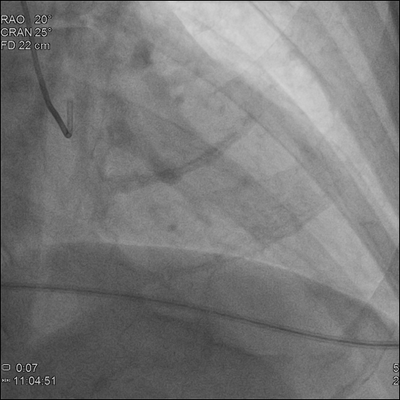

康美醫院介入手術室于12月21日起正式投入使用,該科室位于住院樓四樓,與ICU、手術室相鄰,設置科學、規範,有醫護、患、廢物三通道進出,配備各型尖端設備,其中飛利浦最新型号DSA(數字減影血管造影系統)居省内領先水平。

随後,飛利浦最新型号DSA正式投入使用,知名介入專家、中國醫學科學院阜外醫院趙漢軍主任親臨現場指導介入手術開展。介入手術是一種具有高科技含量的檢查、治療技術,在DSA的引導下,将特制的導管、導絲等精密器械,經血管引入人體,對體内病變部位進行精準診斷和局部治療,爲診斷、治療血管疾病的“金标準”。

在趙漢軍主任的指導下,當天上午成功開展了2台血管造影術,爲患者下一步精準治療提供指導。

我院飛利浦最新型号DSA——“霓彩”FD20全能型大平闆血管造影系統,性能比上一代有大幅提升,采用全新2K*2K影像鏈系統,使微血管和細小病竈得以更加清晰的顯示,讓醫生在血管造影及介入手術中可看到更多的臨床影像細節,助力介入手術精準、安全、順利開展。